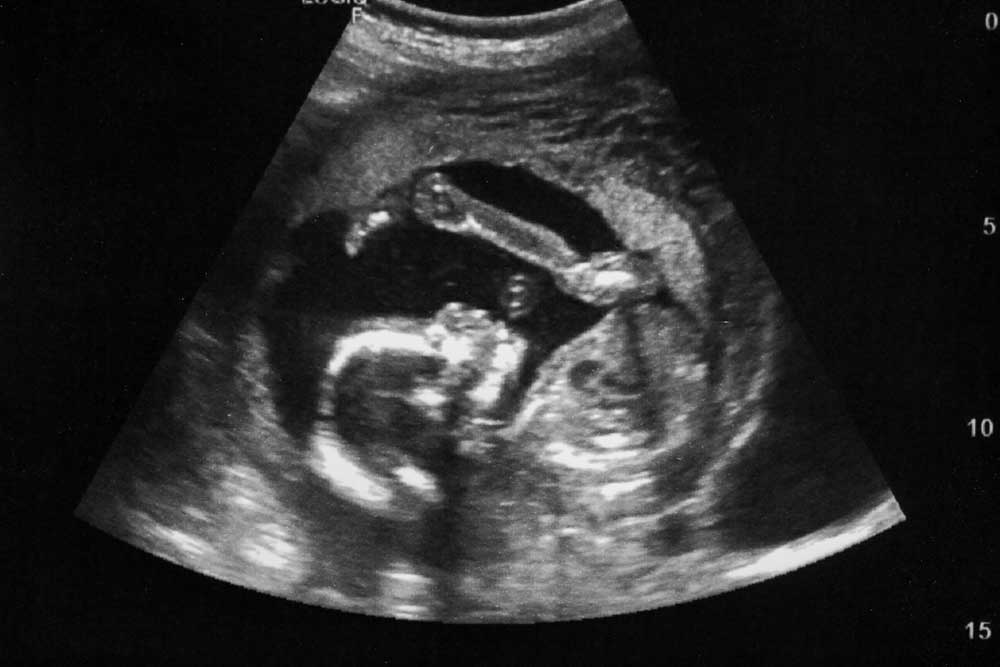

WHAT IS AN ULTRASOUND?

An ultrasound is simply a method of creating an image with the use of high frequency sound waves, so high they cannot be heard by human ears. The sound waves bounce back to the ultrasound equipment to form the image on a monitor. The procedure is totally safe and painless for both you and your baby.

The ultrasound is given after the pregnancy is confirmed and your pregnancy has advanced. If the ultrasound is given too early in the pregnancy the image of the baby will not be defined.